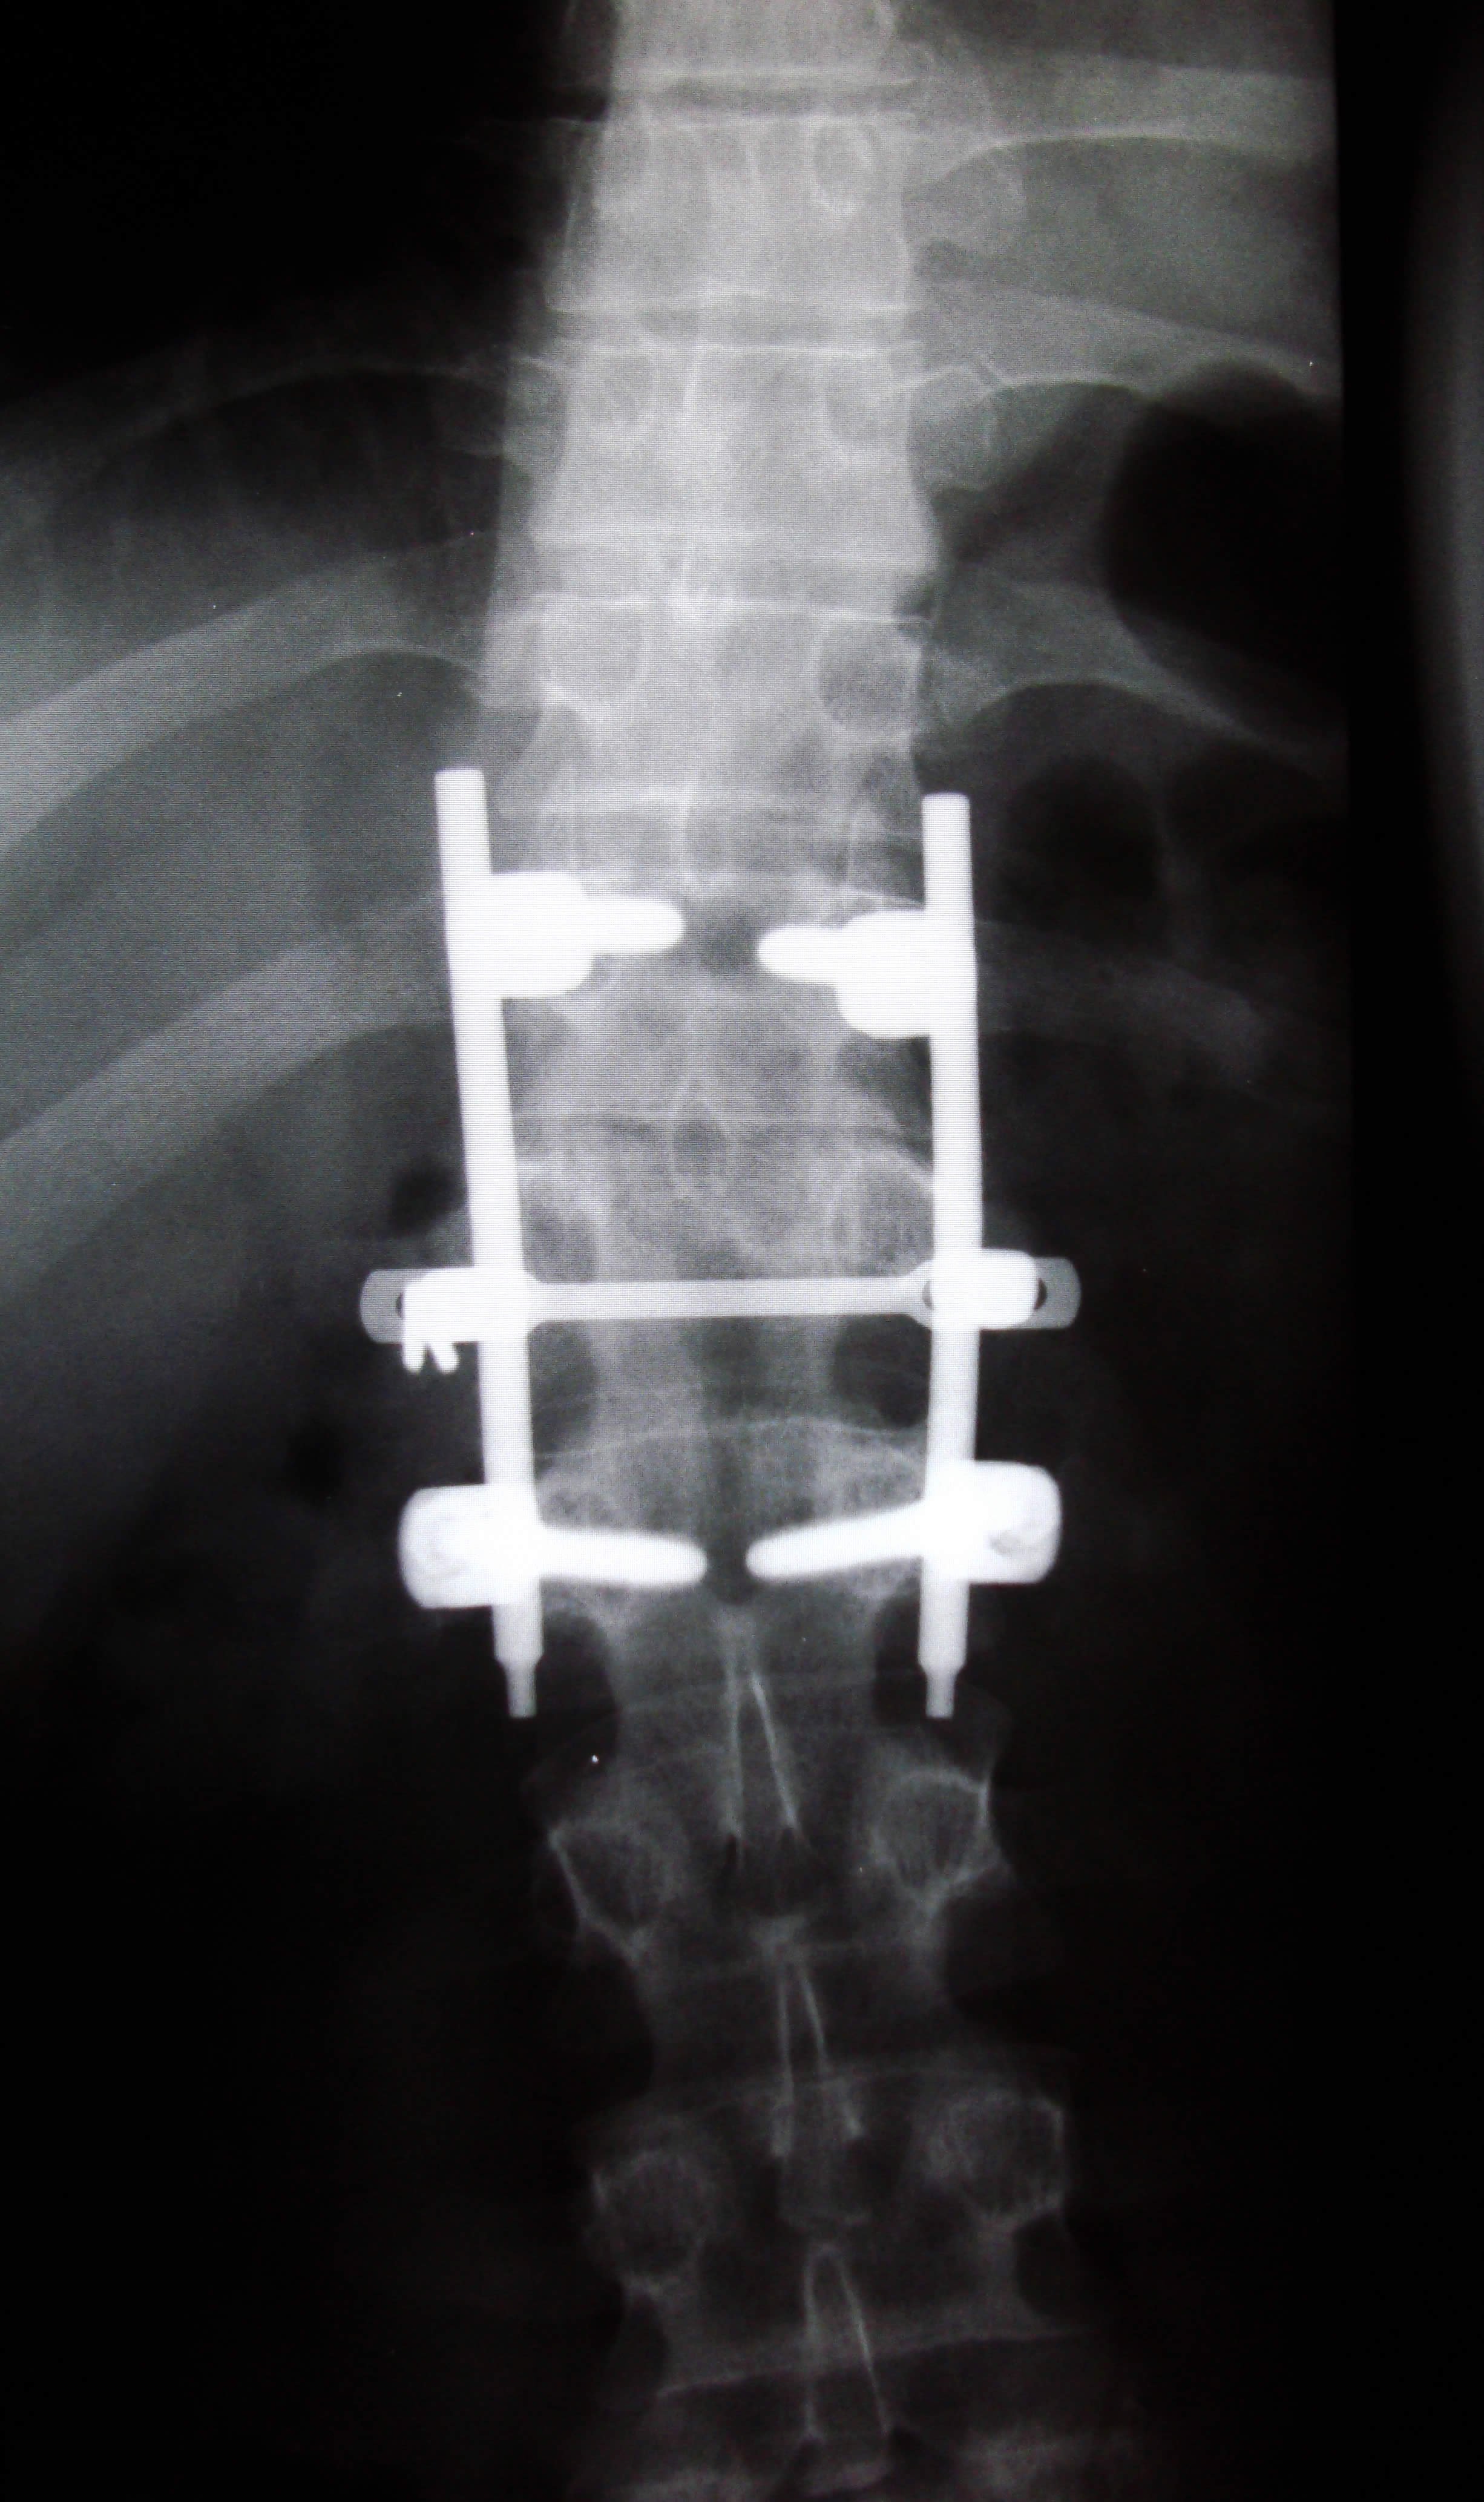

M ost people consider lower back surgery as the last option after all other treatment procedures have offered no relief. Even in such drastic solutions for the desperate measures, back surgery may not provide any significant improvement. Generally, the risks associated with back surgery are low. However, to some people, the risks can be serious. Having knowledge about back surgery beforehand is very helpful because it offers you with a good understanding basis of the risks and benefits and hence decide whether the exercise is a good thing for you or not. Risks; A large number of patients who undergo lower back surgery do not suffer any complications either after or during surgery. Nevertheless, all surgeries bear some level of risk. In general, any back surgery carries the following risks: Bleeding Heart attack Disc herniation Anesthesia Nerve damage Sexual dysfunction Loss of bowel control Loss of bladder control General weakness Instances of blood clots in the lungs or legs Reaction to other drugs Stroke Some risks might be more pronounced in certain people than in others. The degree of risk suffered will also vary contingent to the type of surgery. As part of the surgeon’s responsibility, he or she should assist you establish your risk should a back surgery be performed on you. The best way to know your personal risk is by having a discussion with your doctor before the operation is carried out. The most common type of back surgery for back pain is spinal fusion. In this surgery, the surgeon joins together vertebrae, otherwise called spinal bones. It is aimed at restricting motion occurring between the bones that constitute the spine. Fusion will also limit nerves from stretching beyond some level. Risks associated with spine fusion; Pseudoarthrosis; is the risk that the spinal bones will not fuse together even after the surgery. This risk has however been reduced to about 5 to 10 percent of the surgeries, thanks to modern techniques. Documents from medical literature indicate that smokers have minimal rate of successful vertebrae fusion. The risk of pedicle screws; is the risk of the screws becoming loose or breaking and hence necessitating further surgery to rectify the rods and screws. The risk that the anterior cages and grafts migrate or subside. This will call for a repeat surgery. Another great risk is the failure to eliminate the symptoms of the lower back pain after the surgery. The rate of this risk stands at less than 20% for all the successful operations. Such an outcome is technically referred to as ‘’failed back surgery syndrome’’. [photo: www.flickr.com]